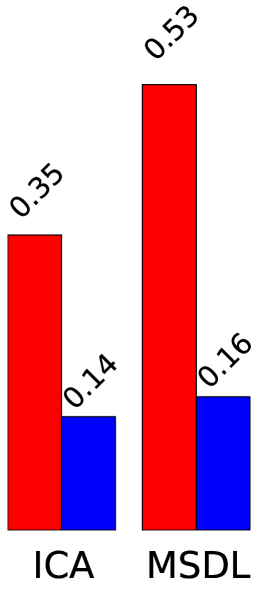

Figure 2 presents region extraction results using each method on the same map. In all figures, the threshold applied during region extraction is shown in a given slice to help understanding. Results for each metric are displayed on the right. We vary parameters for each model (smoothing for ICA, 3 parameters of MSDL) and, for each region extraction method, display the best 10% results across parametrization. Figure 4 shows 2 networks out of 42 extracted.

Stability.

Random Walker dominates the stability metric. It uses local maxima to get regions seeds, and will thus split regions even if they are connected after thresholding. Its performance is statistically significant for both dense and sparse atlases and any parametrization. The stability improvement is larger for sparse than for dense maps. This could be due to the inability of random walker to compensate for the original instabilities of the models.

Data fidelity.